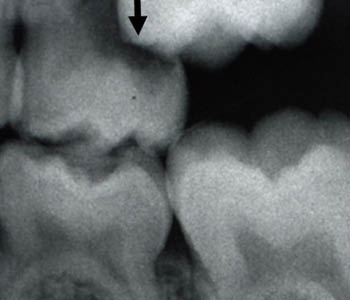

Anterior Crossbite

In the front of the mouth, one or more of the top teeth is stuck behind the bottom teeth.